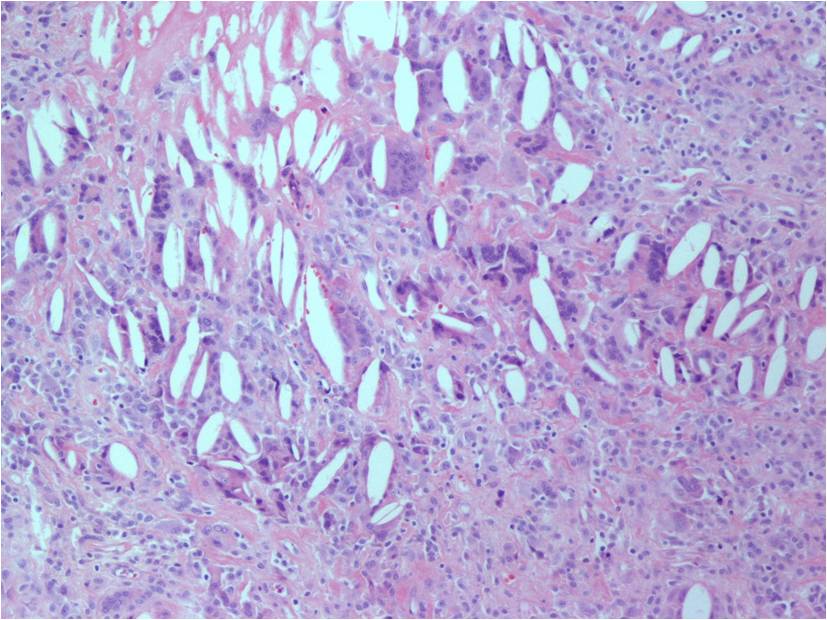

Microscopic (Fig. 12-14)

- Highly cellular

- Lipid Laden Macrophages

- Small polygonal

- Scant cytoplasm

- Spindled cells (with pale cytoplasm)

- Xanthoma cells

- Multinucleated giant cells

- Prominent chronic inflammatory cells

- Foams cells are observed in the periphery of the lesions.

- Hemosiderin pigment prominent

- Stromal and fibroblast cell proliferation

- Numerous cleft-like (alveolar) spaces

- Variable degree of villous, nodular and pigmentation (hemosiderin) and inflammatory components

- Frondlike synovial projections

Fig. 12-14: Highly cellular sheet of spindled cells, multinucleated giant cells and chronic inflammatory cells with variable degree of pigmentation (hemosiderin). Numerous cleft-like spaces or ‘pseudoglandular’ spaces, surrounded by xanthoma cells. Cleft-like spaces are commonly seen in diffuse-type giant cell tumors.